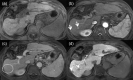

MRI is widely used in clinical practice for detecting liver diseases. Since the introduction of gadoxetic acid, MRI has become the most effective modality for the detection and characterization of focal liver lesions. According to previous meta-analyses, the area under the receiver operating characteristic curve (AUROC) was 0.97-0.99 for the diagnosis of small hepatocellular carcinoma (≥ 2 cm) by gadoxetic-acid-enhanced MRI. Moreover, the AUROC for the diagnosis of colorectal liver metastases was significantly high (0.98). Despite gadoxetic acid's drawbacks, its clinical utility outweighs them, making it the contrast agent of choice in routine liver MRIs. Moreover, clinically, liver MRI has become more prevalent for a quantitative assessment. Liver fibrosis can be evaluated using MR elastography; whereas, hepatic steatosis and iron overload can be evaluated using proton density fat fraction, with high accuracy and reproducibility. This article reviewed the usefulness of liver MRI, which can be a comprehensive imaging modality in clinical practice.